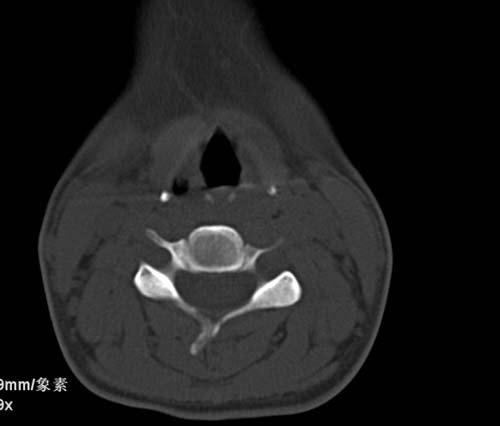

标题: CT22662:女 23 自述双侧颌下腺肿大年余 近来疼痛 左侧明显 [打印本页]

标题: CT22662:女 23 自述双侧颌下腺肿大年余 近来疼痛 左侧明显

见双侧颌下腺略肿大  未见结石及钙化 考虑双侧慢性炎症 ?请指教